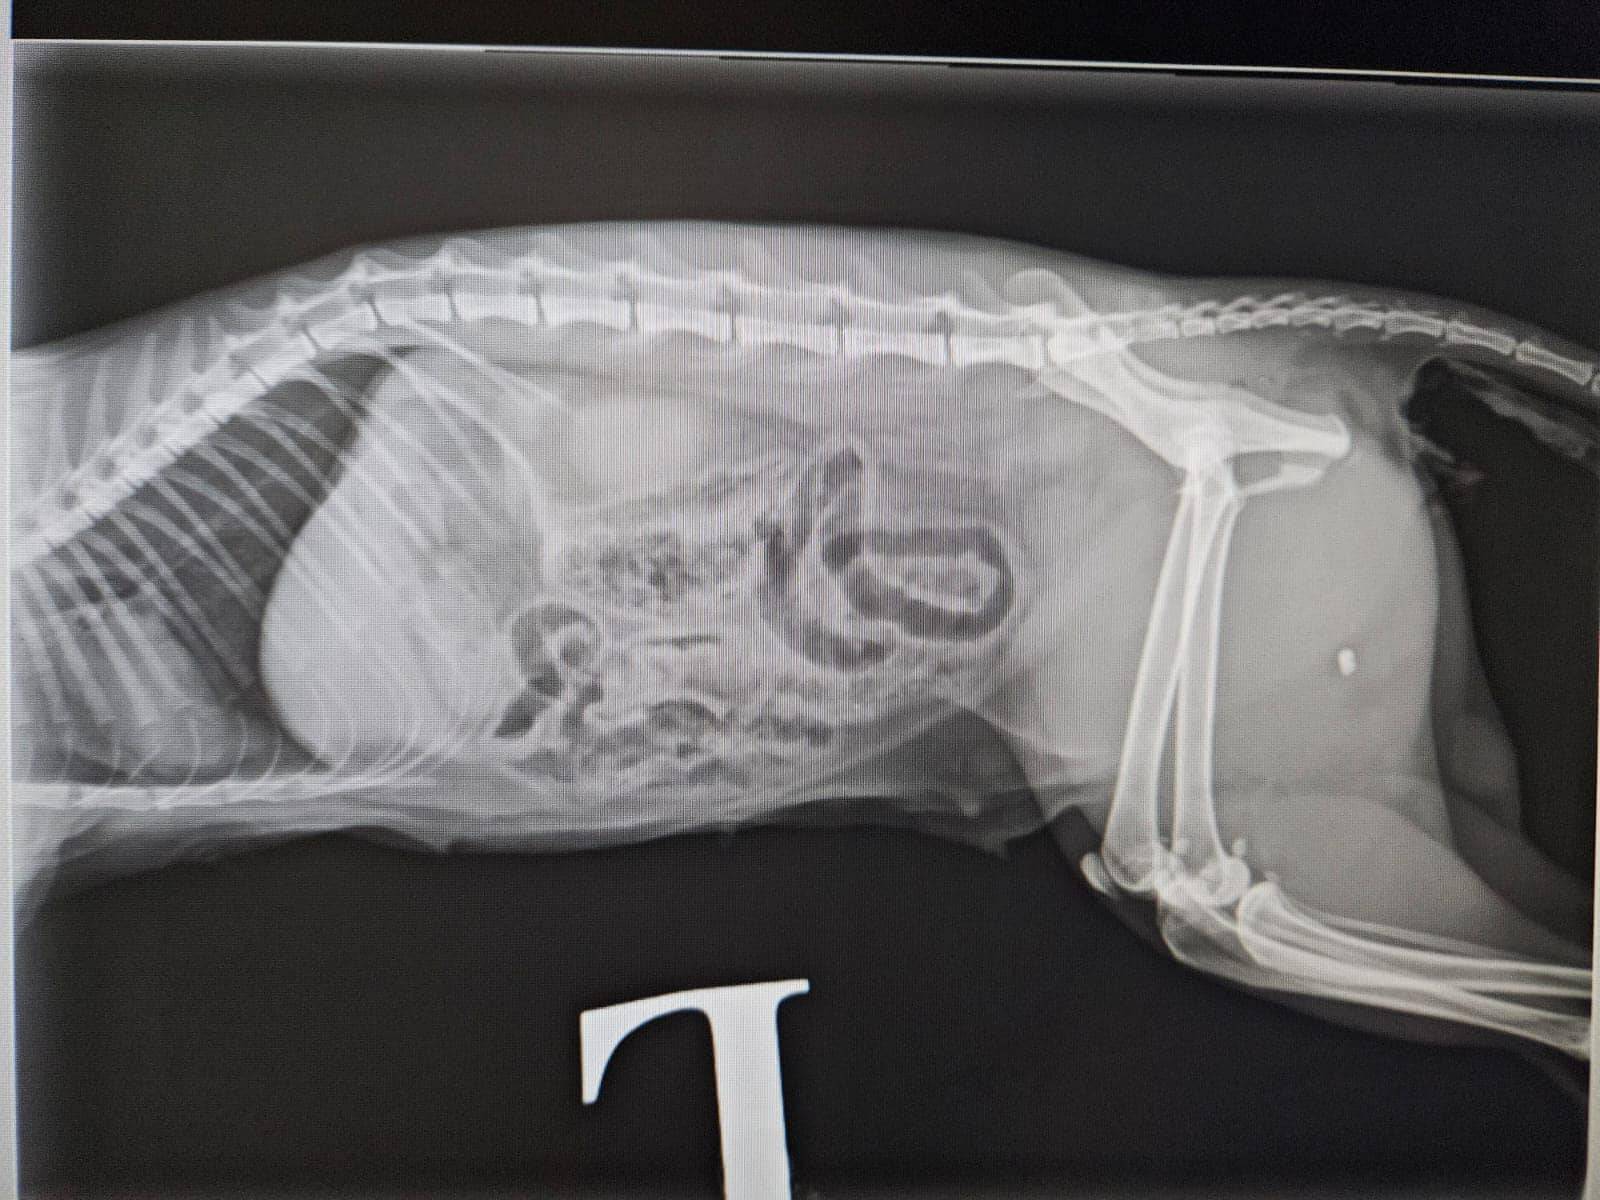

社交平台專頁毛守救援表示,昨晚(10月10日)九時半左右,有唐貓在錦田石崗菜站被一輛白色私家車撞到。受重傷唐貓為貓女,已經絕育及剪耳,頸有蝨帶。貓咪受傷後倒在馬路上,口鼻吐血,大腿有傷口及呼吸急速,情況嚴重,義工到場送院搶救24小時診所搶救。據影片所見,貓咪表情甚痛苦,地上亦留下大量血跡。